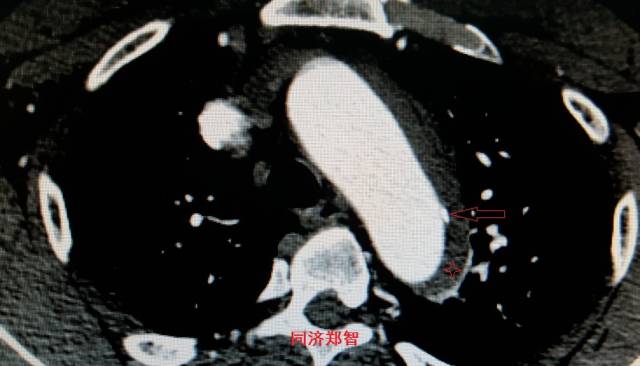

病例五

平扫CT提示主动脉弓层面及右肺动脉层面均可见主动脉血管腔内的内膜片影(红色箭头所示),CTA显示为A型主动脉夹层。

图8-11